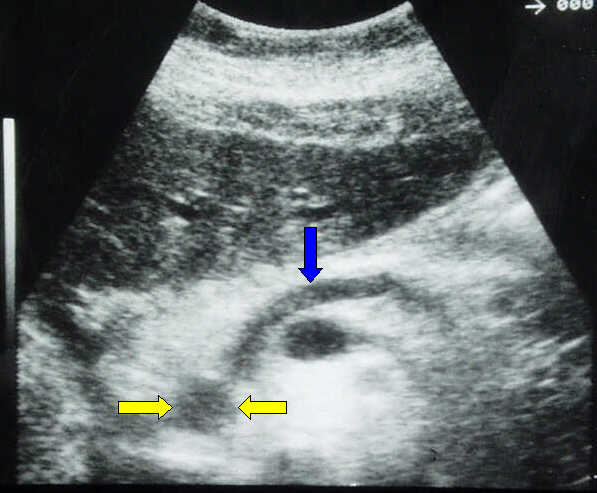

Transverse

scan. Small (12 mm), rather homogeneous, poorly reflecting cancer of the

pancreatic head (yellow arrows) causing evident dilatation of the main pancreatic

duct (blue arrow).